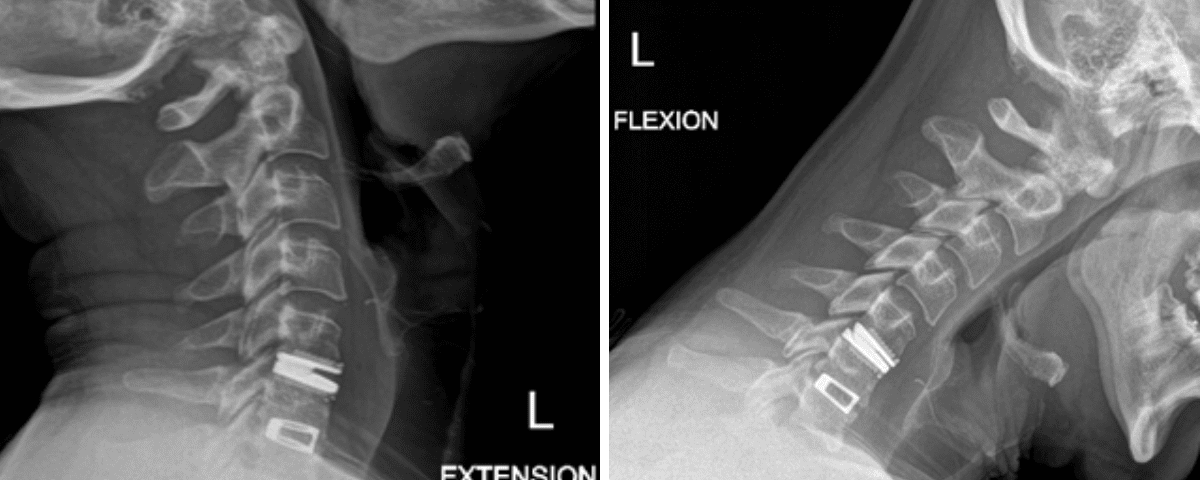

He had no neurologic deficits on exam, and therefore was started on a trial of multidisciplinary and multimodal conservative management. This included non-opioid pharmacologic regiment, lifestyle modification, physiotherapy, chiropractic, and epidural steroid injection. Despite these conservative measures, his symptoms remained severe and debilitating, and therefore surgical options were discussed. He underwent an uneventful C5-6 anterior artificial disc replacement. Postoperatively, his neck and radicular arm pain had fully resolved. Imaging demonstrated maintained physiologic flexion and extension of the cervical spine (Figure 2). This motion-preserving surgery reduces the adjacent degeneration process, and the need for further surgeries down the line.

Figure 2: Postoperative dynamic xrays; note the differences in range of motions between the artificial disc at C5-6 and the previous fusion at C6-7.